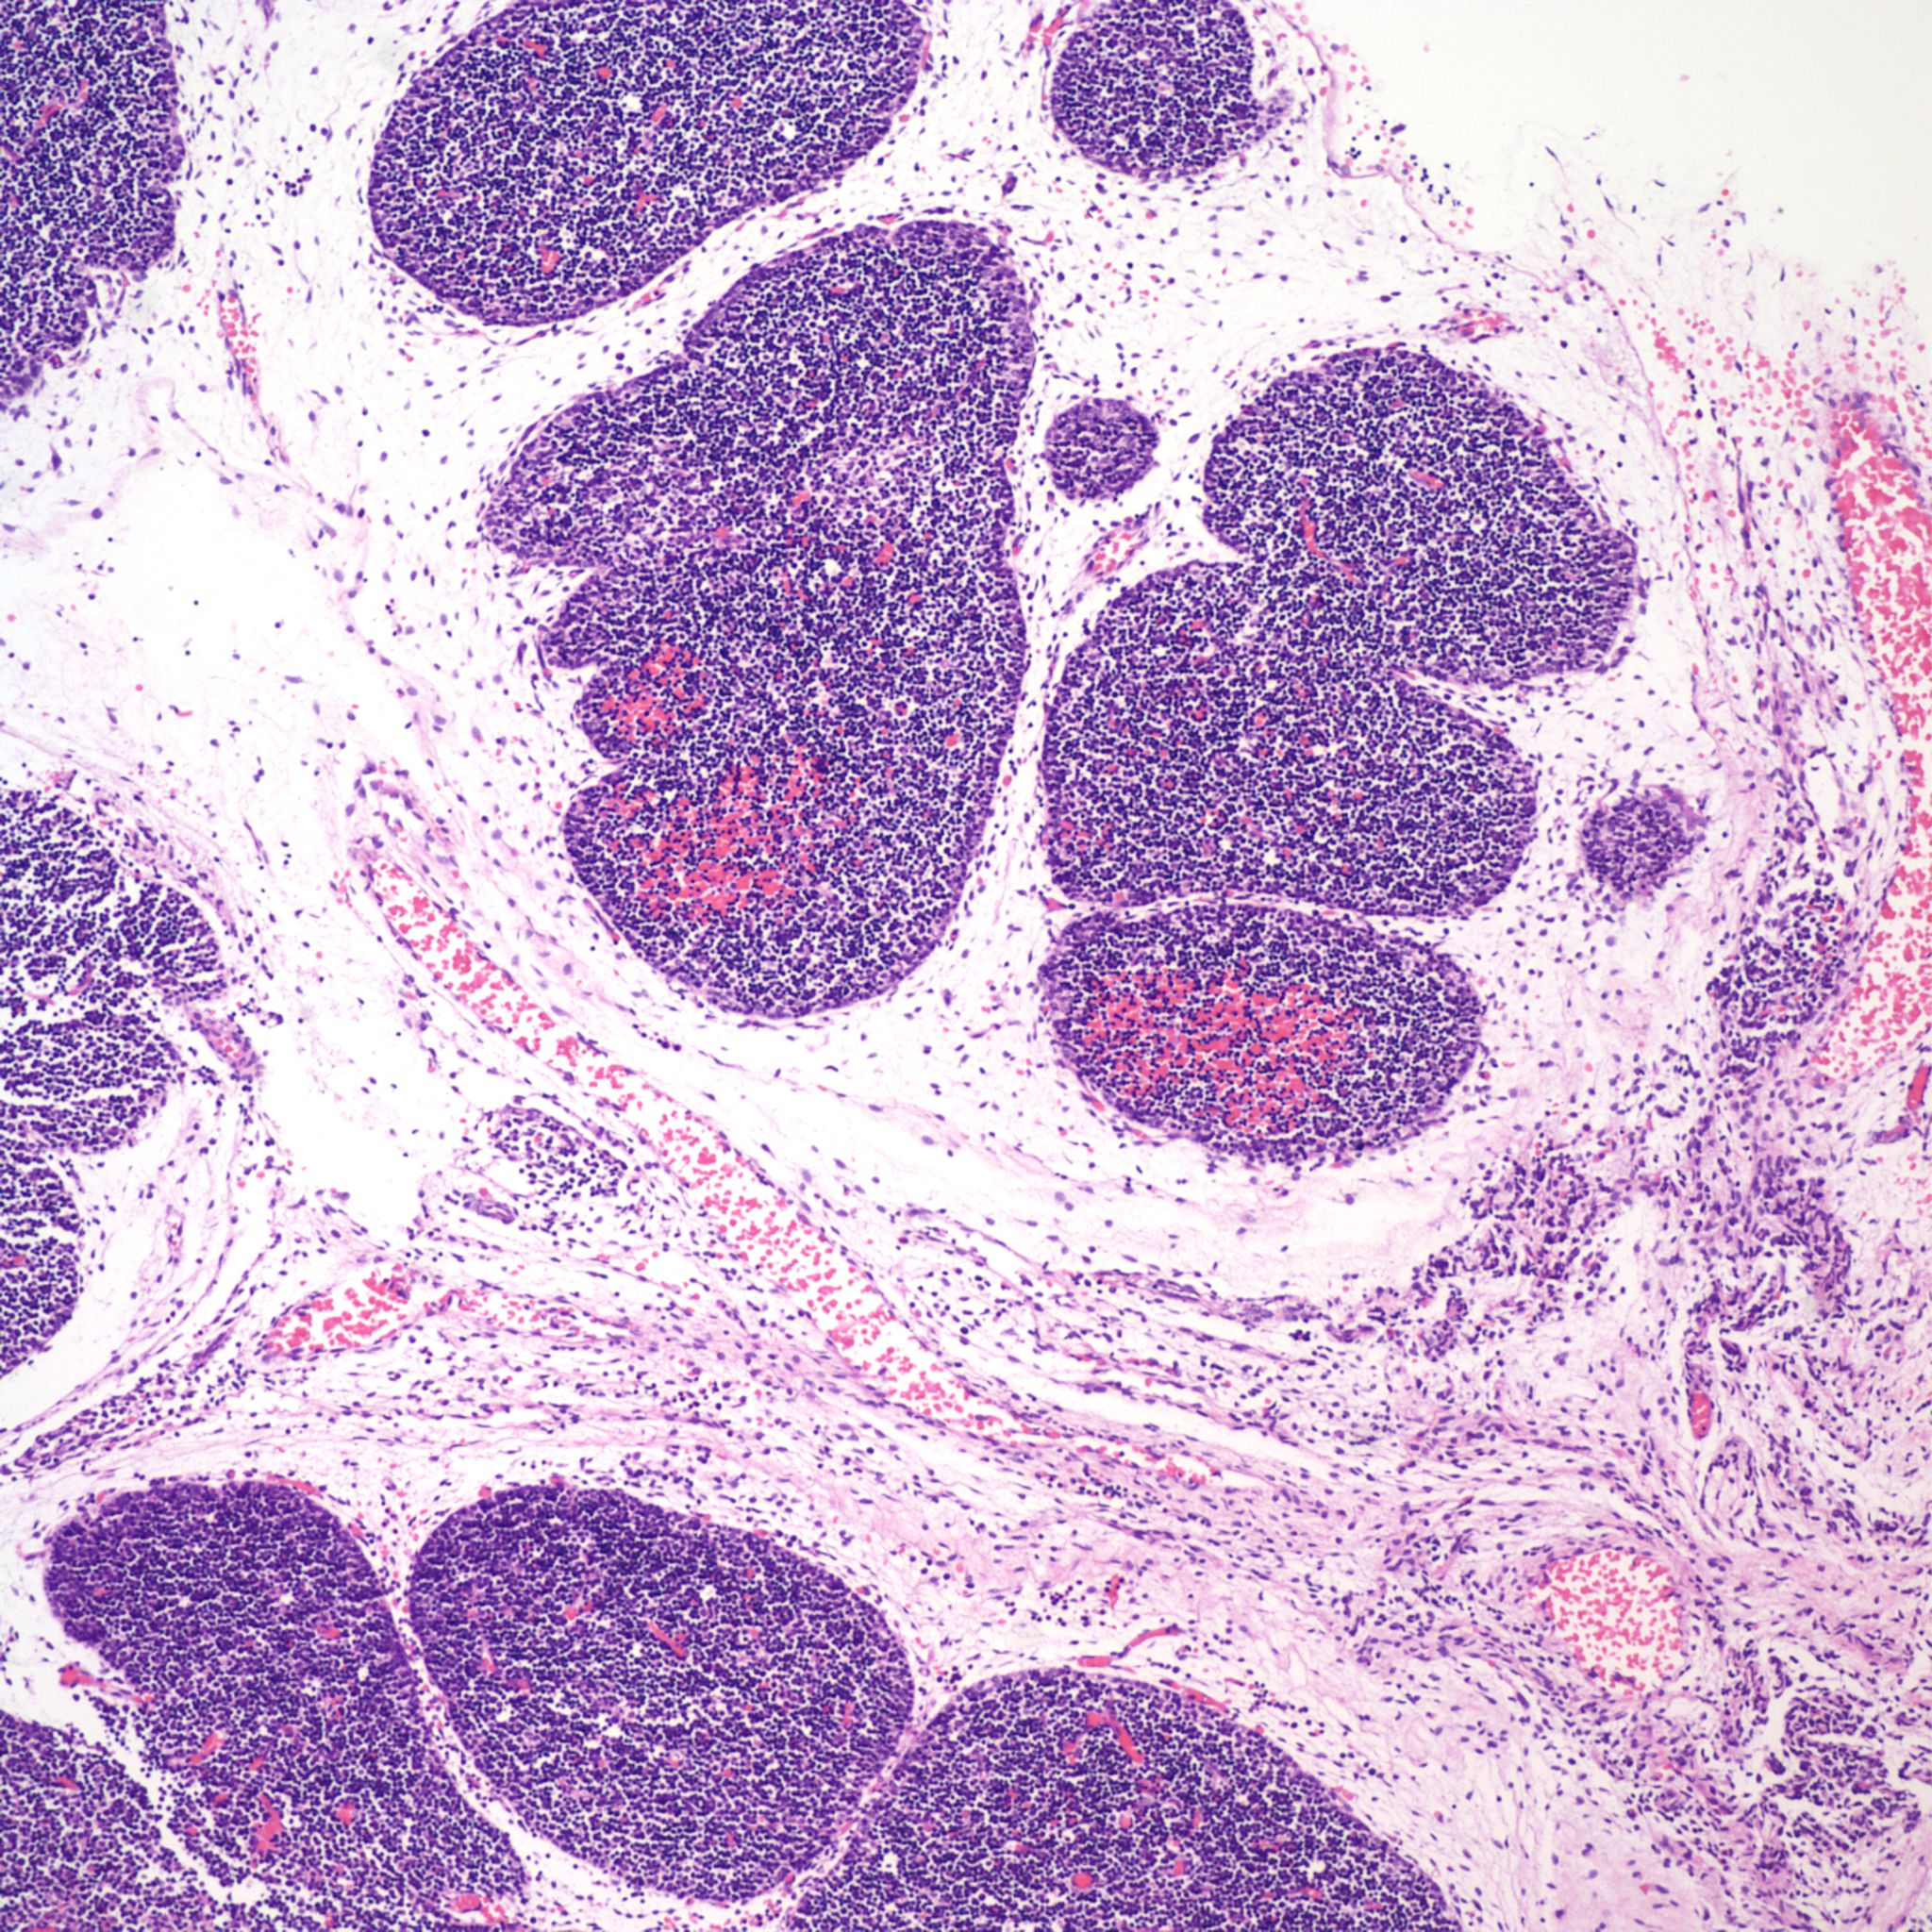

2. Thymic Involution

The thymus normally involutes as the infant ages. However, in some stillborn infants, usually with a chronic stress such as infection, fetal hydrops or growth restriction, there is accelerated involution, that is loss of the lymphocytes in the cortex of the thymus. An early phase of this process is often seen in response to chorioamnionitis. In the acute cases, the prominent abnormality is a “starry sky” appearance due to the lymphorrhagia (phagocytosis) of cortical lymphocytes. Low magnification microscopy demonstrates open spaces in the cortex reminding some observers of a “starry sky”. (Fig 9,10) At higher magnification, these apparent spaces can be seen to be the cytoplasm of a large cell often with small, fading nuclei of small lymphocytes within.

As involution progresses, there will be a progressive loss of cortical lymphocytes. The cortex will appear notably thinned compared to the medulla with thinner lobules and more connective tissue between lobules (Figs 11a, 11b, 12a, 12b, 13a, 13b).